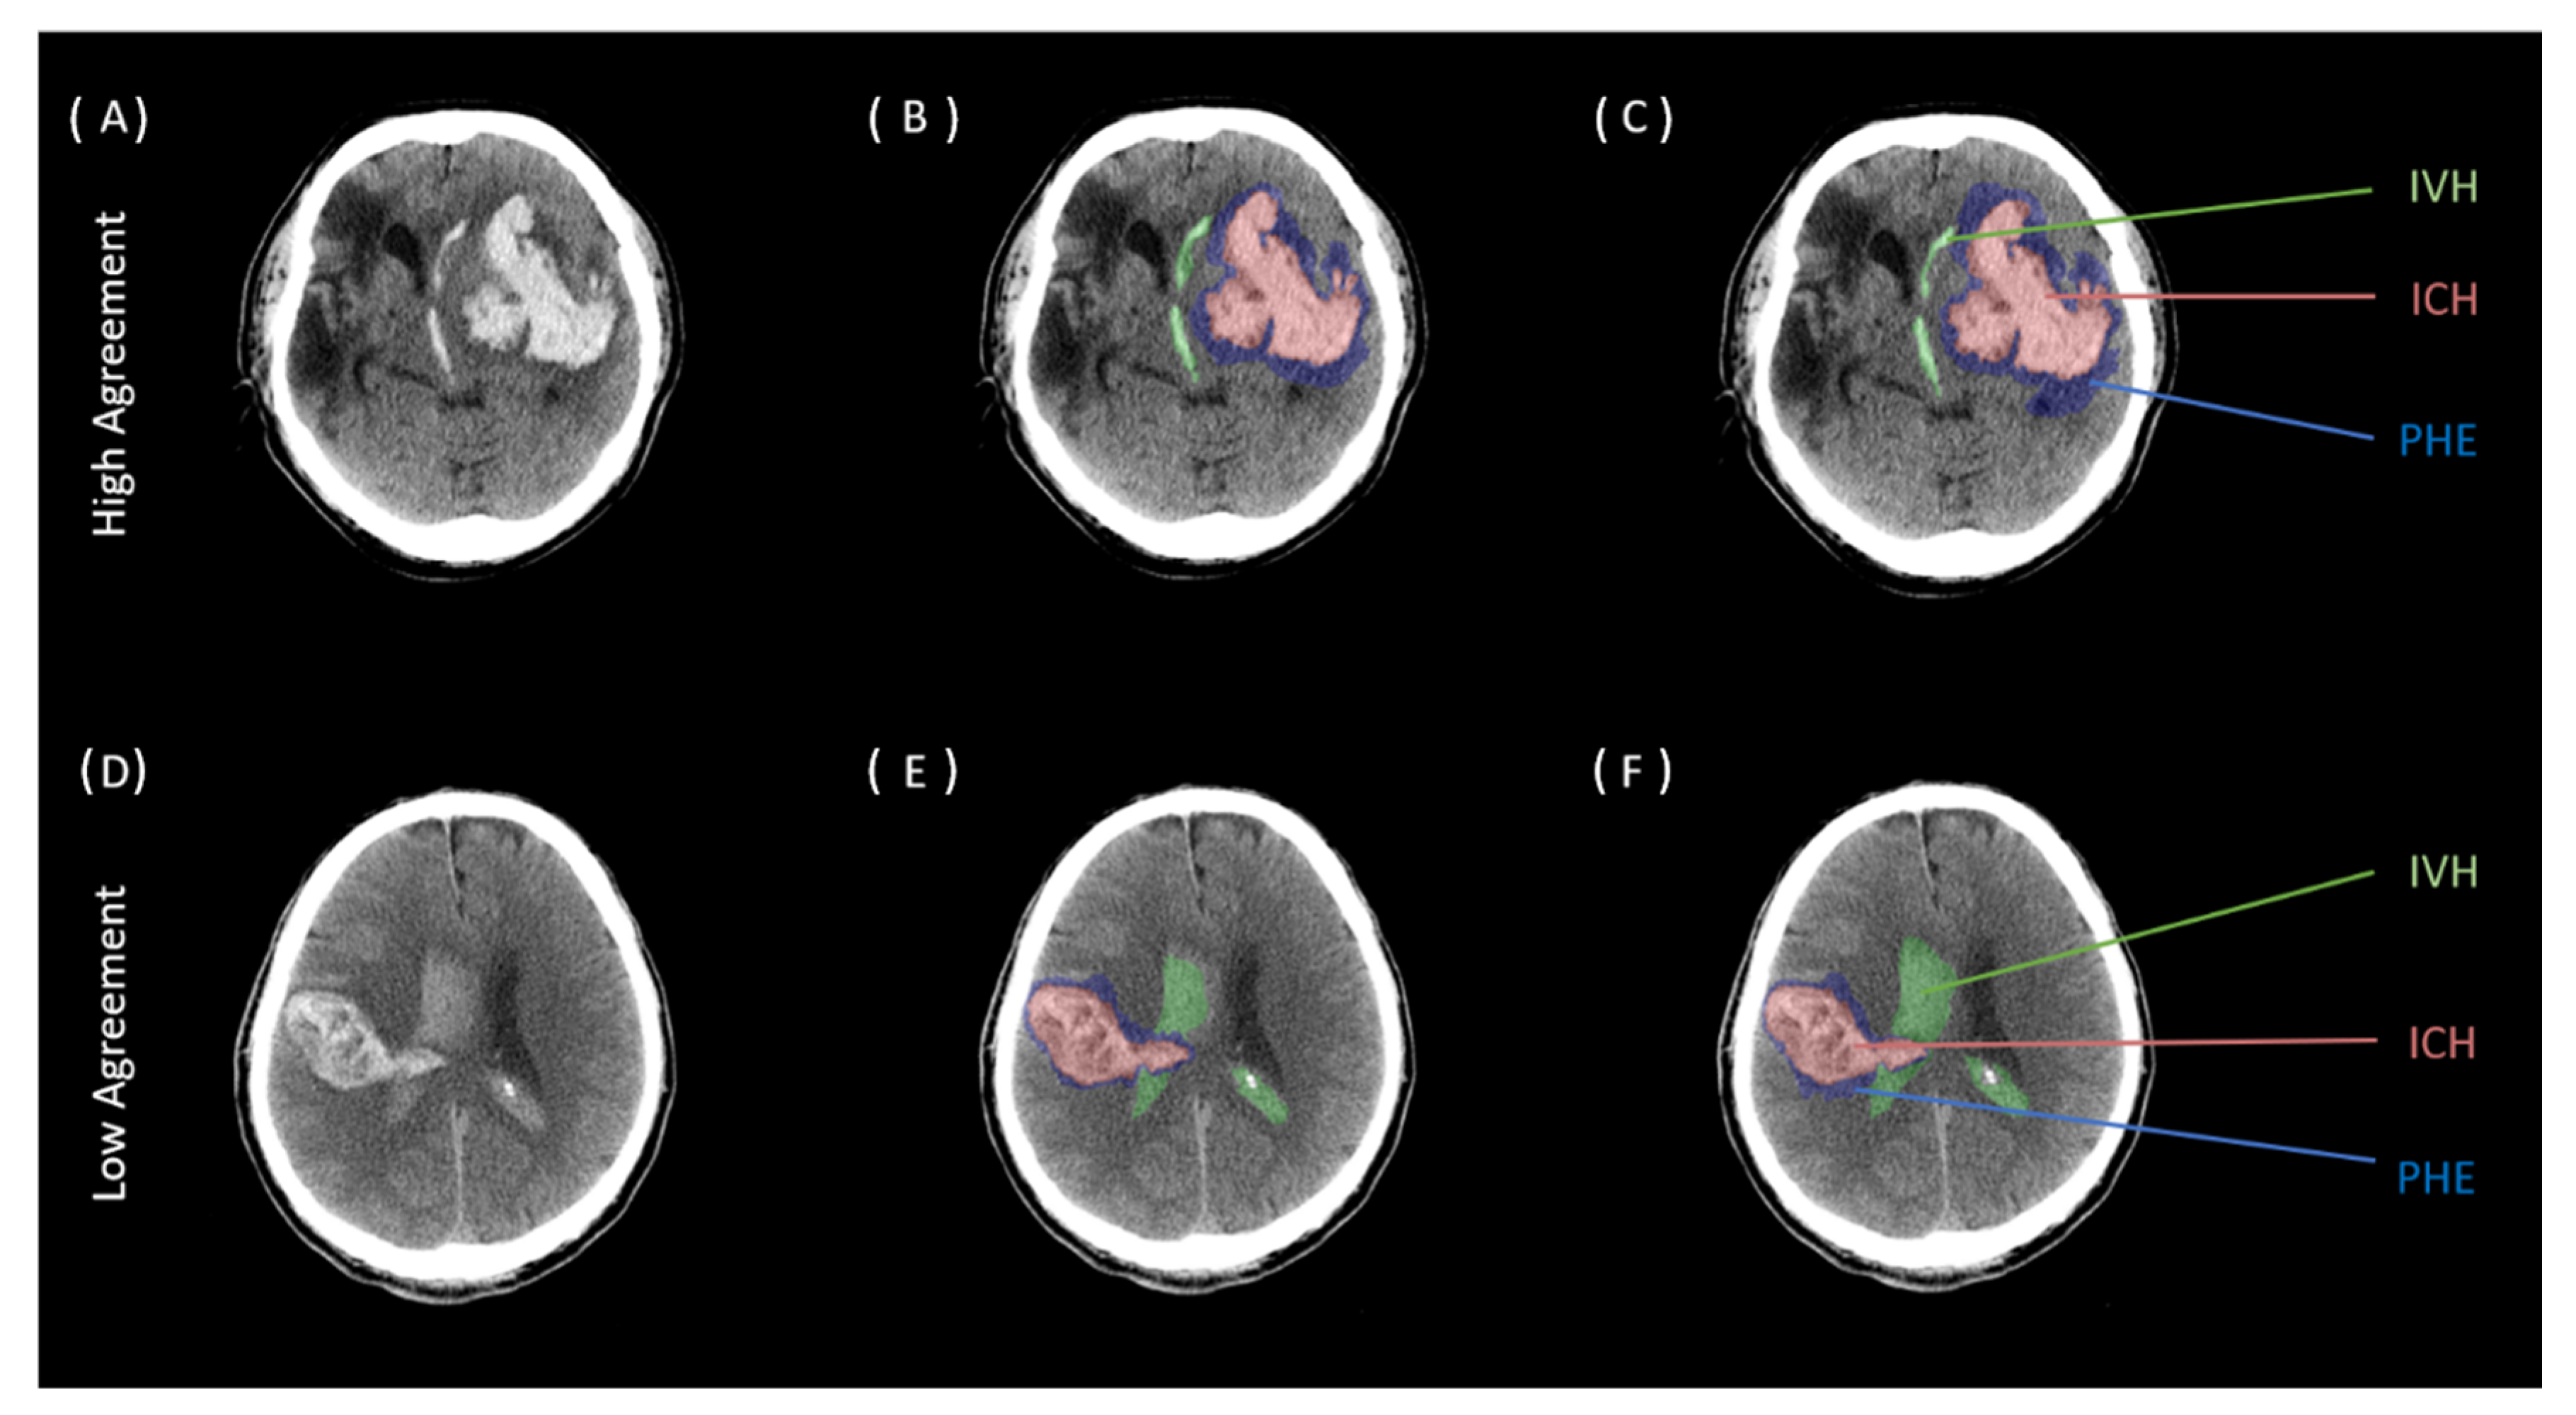

2.3. Image Analysis

3. Results